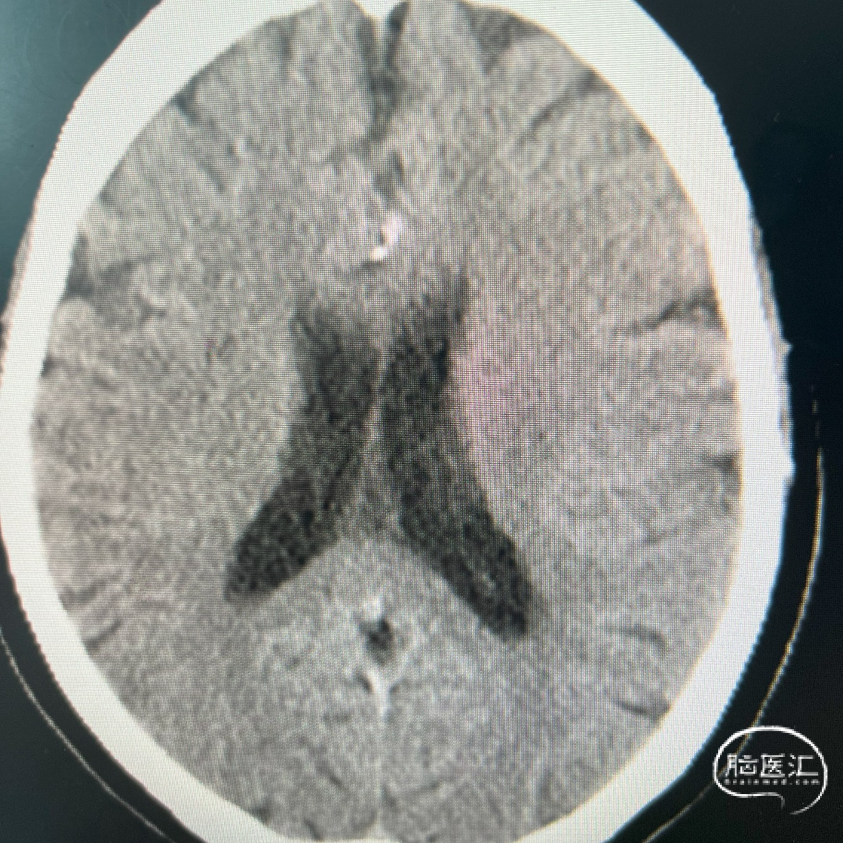

术前影像资料

术前辅助检查:

术前FLAIR

术前DWI

术前MRA

影像学表现:

1、主动脉弓及其他弓上血管,III型弓,弓上血管迂曲,血管通畅。

2、颈内动脉系统:

右侧颈总动脉及颈内动脉血管通畅,远端右侧大脑中动脉血流通畅,可见同侧及对侧大脑前动脉显影。

左侧颈总动脉及颈内动脉血流通畅,后交通开放,可见同侧大脑后动脉显影,大脑前动脉血流通畅。

3、椎基底动脉系统:

右侧椎动脉优势型。

左侧椎动脉血管纤细,远端可见基底动脉浅淡显影。

右侧椎动脉优势型,远端汇入基底动脉。

基底动脉中段重度狭窄,狭窄率约80%,双侧大脑后动脉可见显影。

术前DSA影像:

复查Dyna CT,颅内未见出血及造影剂外渗。